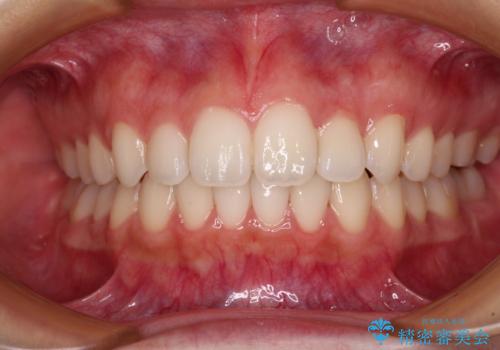

カリエール・ディスタライザーを併用したインビザライン矯正治療

カリエール・ディスタライザーを用いたことで上顎前歯の突出感はスムーズに解消され、歯列不正は1年半ほどでほぼ改善することができました。

しかし、その後インビザライン特有の奥歯がうまく噛めないという問題が長引き、改善に1年近い期間を要することとなりました。